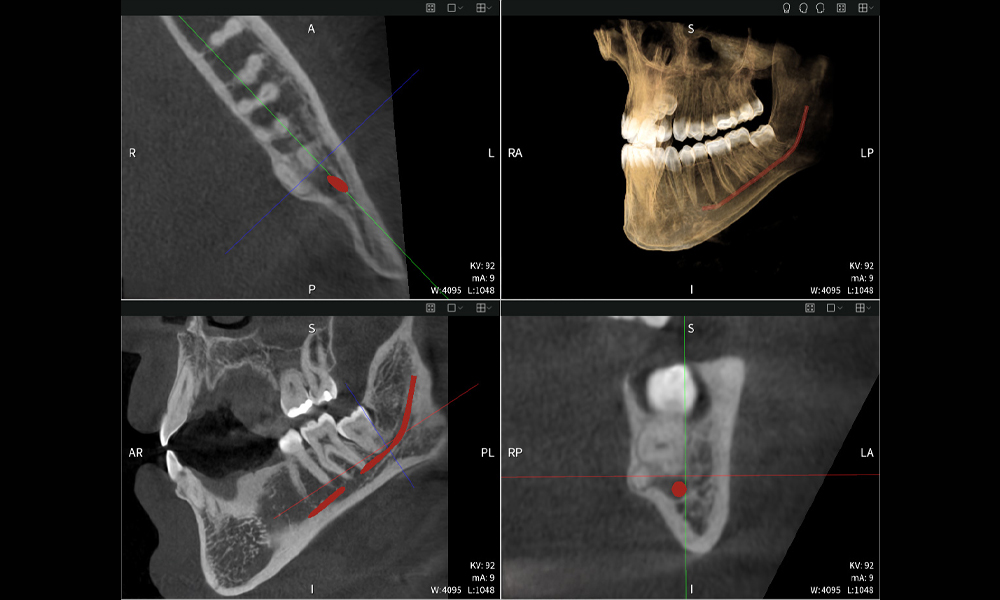

Abbildungen b–d zeigen verschiedene Ansichten einer 3D-Rekonstruktion des Unterkiefers und bieten eine umfassende Übersicht über die Anatomie des Unterkiefers, die Lage der Nerven im Verhältnis zu den Zähnen und ermöglichen die Beurteilung der Zahnsymmetrie und Ausrichtung.

Abbildung d zeigt den bereits vorbehandelten Zahn 48, dessen Krone entfernt wurde und dessen Wurzeln nahe am Nerv belassen wurden, was das hohe Risiko einer Nervenschädigung verdeutlicht.

Abbildung e: Panoramaröntgenaufnahme dient der initialen Beurteilung und zeigt die allgemeine Zahnstellung sowie mögliche pathologische Veränderungen auf. Insbesondere ist auf der rechten Seite (Zahn 48) die Situation nach einer Kronenamputation durch einen externen Behandler ersichtlich. Die beiden stark gekrümmten Wurzeln verbleiben in enger topographischer Beziehung zum Nervus alveolaris inferior im Knochen. Dies deutet auf eine bewusste Entscheidung zur Vermeidung eines erhöhten Risikos einer Nervenläsion während einer vollständigen Extraktion hin und stellt einen klinisch relevanten Befund dar. Zusammenfassend liefern die CBCT-Aufnahmen mit Seethrough Max entscheidende Informationen über die komplexe Anatomie und die kritische Beziehung zwischen den Weisheitszähnen und dem Nervus alveolaris inferior. Diese detaillierte präoperative Diagnostik ist unerlässlich für die sichere und erfolgreiche Durchführung chirurgischer Eingriffe im Unterkieferbereich.